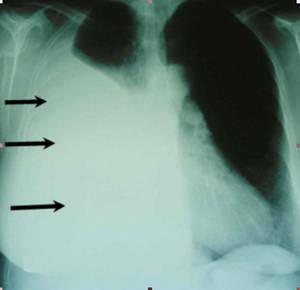

Häufige Symptome sind Luftnot und Schmerzen im Brustkorb. Untersuchungs-möglichkeiten bestehen in der Lungenfunktionsmessung und Röntgenaufnahmen (siehe Abb. 1). Weiterhin können eine Computertomographie (CT) Sonographie (Ultraschalluntersuchung), Magnetresonanztomographie, Pleurapunktionen, Spiegelung des Brustkorbes (Thorakoskopie, siehe Abb. 2) sowie die Entnahme von Gewebeproben  erforderlich sein.

Abb1: Röntgenaufnahme mit Pleuraerguss rechts